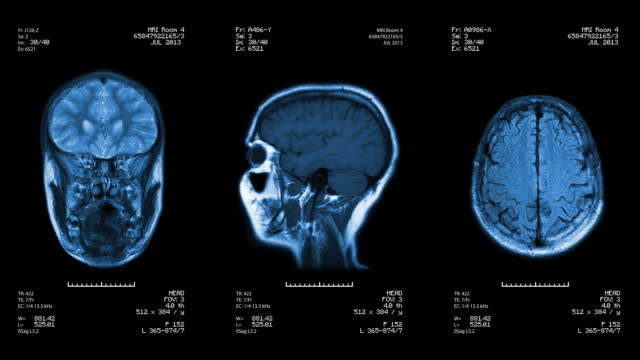

뇌경색 초기증상 치료방법

급성 뇌경색의 치료는 뇌에 있는 세포 파괴를 최소화하기 위해 빠르게 시행되어야 합니다. 즉시 응급실을 찾아가면, 4.5시간 이내라면 정맥주사를 통해 혈전용해제제를 투여하는 것이 일반적인 치료입니다. 경동맥이나 큰 뇌 혈관이 막힌 경우에는 혈관 내 재개통술을 시행하여 혈전을 제거하는 것이 필요합니다. 만약 이런 치료가 실패하거나 다른 치료가 필요한 경우, 혈관문합술과 같은 치료도 고려될 수 있습니다.